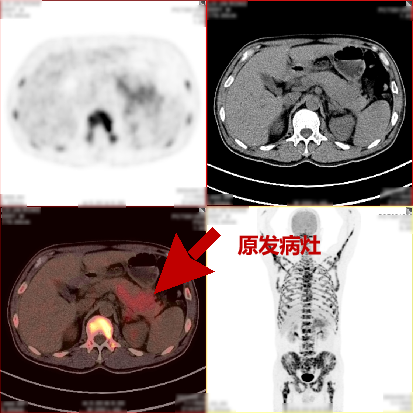

病史:男,55岁,腹痛伴乏力3天入院检查,MR:胰尾部肿物,考虑胰腺癌并多发淋巴结转移;超声胃镜下胰腺活检未见癌细胞,为了解全身状况申请PET检查。

PET/CT检查所见

空腹 6h 以上,静脉注射显像剂 18F-FDG,平静休息 60min 后行全身 PET 及 CT 断 层显像,解剖与功能图像行多层面、多幅显示,影像清晰。

PET/CT诊断意见:

1、胰腺体尾部块状胰腺癌,病灶侵犯相邻胃体部胃壁,并可能侵犯左侧肾周筋膜,肿块远端胰尾部胰管扩张;盆腔少量积液;

2、胰腺尾部周围、中上腹部腹膜后区腹主动脉周围及纵隔内(1R、1L、2R、4R、5、7 组)多发淋巴结转移灶;

3、双侧尺骨近端、双侧肱骨、右侧颞骨、枕骨、蝶骨、双侧下颌骨头、双侧锁骨、双侧肩胛骨、胸骨、脊柱各椎体、双侧各肋骨、骨盆诸组成骨、右侧股骨头、双侧股骨颈及股骨干广泛骨转移灶,其中左侧第 2、4 前肋、右侧第 4、7 侧肋病理性骨折。

PET/CT活检病理:胰腺癌